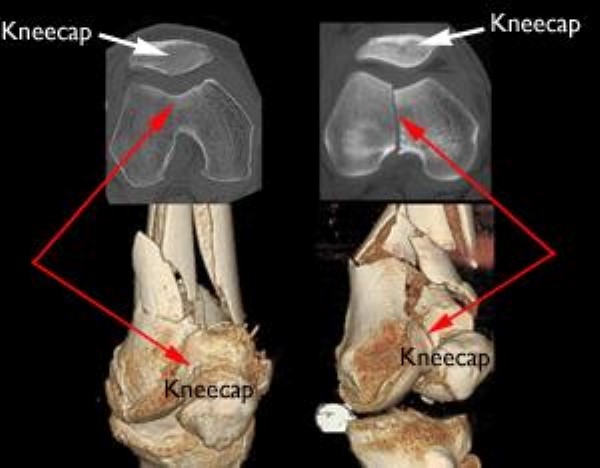

• Computed tomography (CT) scan. A CT scan shows a cross-sectional image of your limb. It can provide your doctor with valuable information about the severity of the fracture. This scan can show whether the fracture enters the joint surface and, if so, how many pieces of bone there are. A CT scan will help your doctor decide how to fix the break.

CT scans and 3-dimensional models of distal femur fractures

CT scans provide cross-sectional and 3-D images. In this illustration of two separate fractures, the cross-sectional image has been placed above its corresponding 3-D image. The distal femur fracture on the left has not broken the weightbearing part of the bone. The fracture on the right, however, has broken the joint surface into two pieces.